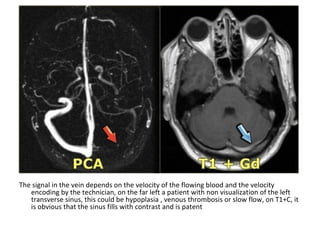

The signal in the vein depends on the velocity of the flowing blood and the velocity

encoding by the technician, on the far left a patient with non visualization of the left

transverse sinus, this could be hypoplasia , venous thrombosis or slow flow, on T1+C, it

is obvious that the sinus fills with contrast and is patent